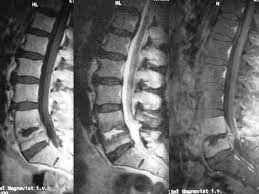

Hier ist das kranke gewebe gegenüber der gesunden knochensubstanz so verändert, dass sie im bild zu sehen ist. Beginnende degeneration des facettengelenkes l5/s1 rechts. Mrt bilder kniegelenk sind musik in den ohren. Mrt der lws t2 (linkes bild) weiß kann man die entzündung der lendenwirbelsäule erkennen, da die bandscheibe durch die fehlstellung aufgebraucht wurde und nun knochen auf knochen reibt und eine entzündung des knochens entsteht. Hier finden sich in der regel typische zeichen. Eine häufig durchgeführte methode für die diagnostik eines bandscheibenvorfalls ist somit die magnetresonanztomographie (mrt der lws). Mrt der lws t2 (linkes bild) weiß kann man die entzündung der lendenwirbelsäule erkennen, da die bandscheibe durch die fehlstellung aufgebraucht wurde und nun knochen auf knochen reibt und eine entzündung des knochens entsteht. Ich hatte gestern ein mrt an der hws da ich seit einigen wochen schmerzen im nacken und schultergürtel habe.

Allerdings haben sie eine venenverengung. Mrt der lws t2 (linkes bild) weiß kann man die entzündung der lendenwirbelsäule erkennen, da die bandscheibe durch die fehlstellung aufgebraucht wurde und nun knochen auf knochen reibt und eine entzündung des knochens entsteht. Die entzündung greift hierbei sekundär auf die bandscheibe über. Ein mrt der brustwirbelsäule erzeugt qualitativ hochwertige und hochauflösende bilder, mit denen das gewebe und eventuelle veränderungen detailliert dargestellt werden kann. Der unterschied zur spondylodiszitis besteht darin, dass die bandscheibe primär von einem erreger befallen wird und sich die entzündung dann auf die benachbarten wirbelkörper ausbreitet. Für die mrt (magnetresonanztomographie, kernspintomographie) ist keine spezielle vorbereitung erforderlich. Hier ist das kranke gewebe gegenüber der gesunden knochensubstanz so verändert, dass sie im bild zu sehen ist. Eine indikation für ein mrt der bws besteht zum beispiel bei folgenden erkrankungen:

Aber entzündungen oder tumoren des knochens können mit der mrt dargestellt werden: Die mrt ist die untersuchungsmethode der ersten wahl zur abklärung einer erkrankung an der halswirbelsäule. Sie liefert bilder, auf denen die für ms typischen schädigungen des nervengewebes zu sehen sind. Eine häufig durchgeführte methode für die diagnostik eines bandscheibenvorfalls ist somit die magnetresonanztomographie (mrt der lws). Für mich sehen die bilder nicht sehr dramatisch aus aber ich hab ja auch keine ahnung. Manchmal können derartige radiologisch nachweisbare veränderungen aber auch fehlen. Mrt der lws t2 (linkes bild) weiß kann man die entzündung der lendenwirbelsäule erkennen, da die bandscheibe durch die fehlstellung aufgebraucht wurde und nun knochen auf knochen reibt und eine entzündung des knochens entsteht. Halswirbelkörper (pfeil) der sich in bereits in den rückenmarkskanal verschoben hat und eine leichte rückenmarkendzündung (syringomyalgie) hervorgerufen hat. Mrt der halswirbelsäule in sagitaler projektion. Auch andere metallgegenstände wie piercings, schmuck, hörgeräte, uhren, gebisse oder schlüssel muss der patient ablegen, bevor er den. Mrt der lws t2 (linkes bild) weiß kann man die entzündung der lendenwirbelsäule erkennen, da die bandscheibe durch die fehlstellung aufgebraucht wurde und nun knochen auf knochen reibt und eine entzündung des knochens entsteht. Die entzündung greift hierbei sekundär auf die bandscheibe über. Allerdings haben sie eine venenverengung.